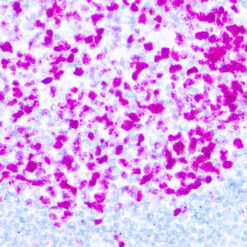

Solitary fibrous tumor (SFT) is a fibroblastic neoplasm of variable biologic potential that can arise at a wide range of anatomic sites. Almost all cases of (98%) including conventional, cellular, atypical, and malignant variants showed nuclear expression of STAT6. Staining for STAT6 was usually diffuse: 68% of cases showed reactivity for STAT6 in 75% of tumor cells. Further, the intensity of staining was strong in 67% of cases, moderate in 25%, and weak in only 7%. The heterogeneity of staining, both in terms of extent and intensity, which may be because of uneven tissue fixation or loss of antigenicity in older cases for which the unstained slides were stored for extended periods of time. All other tumor types examined were negative for STAT6, except for three dedifferentiated liposarcomas and one deep fibrous histiocytoma, which showed weak staining. STAT6 is therefore a highly sensitive and almost perfectly specific immunohistochemical marker for SFT, and can be helpful to distinguish this tumor type from histologic mimics.